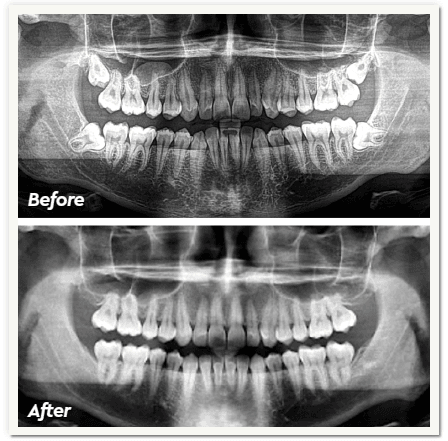

This is a typical case involving a patient who presented with a deep bite and maxillary and mandibular crowding. His primary concern was achieving straight teeth, which provided me with an ideal opportunity to test Clarity Aligners. The treatment consisted of 24 aligners over the course of 6 months.

This patient’s treatment progressed without the need for refinements, and he was extremely happy with the final results. Based on this experience, Clarity Aligners are my now my preferred choice to offer my patients when discussing aligner treatment. The ease of use and reliability of Clarity Aligners have made a positive impact on my practice and patient satisfaction.